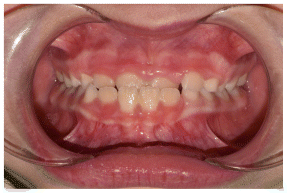

The patient was a young female presenting with a Class III dento-skeletal malocclusion, which was treated using the AMCOP® TC appliance. A comprehensive diagnostic protocol was carried out both before and after treatment, including orthopantomography (Figure 2–3), postero-anterior teleradiography (Figures 4, 5), latero-lateral cephalometric radiography (Figures 6, 7), cephalometric analysis (Tables 1, 2), as well as extraoral (Figures 8, 9) and intraoral photographs (Figures 10, 11). The extraoral examination revealed an edge-to-edge incisal relationship and the presence of a midline diastema. Pre-treatment cephalometric analysis (Deltadent® Lana, Bolzano, Italy) confirmed the diagnosis of a skeletal Class III malocclusion. The treatment plan involved the use of the AMCOP® TC appliance. The patient was instructed to wear the device for two hours in the afternoon and throughout the night for the first six months, followed by nighttime use only for an additional six months. Upon completion of the treatment, the patient achieved a Class I occlusion, with correction of both overjet and overbite. Additionally, the device facilitated tongue re-education and contributed to the postural realignment of the first cervical vertebra.